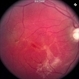

- Mike Mackens

- Imaging device

- Fundus camera

- Severe traction retinal detachment with diabetic retinopathy